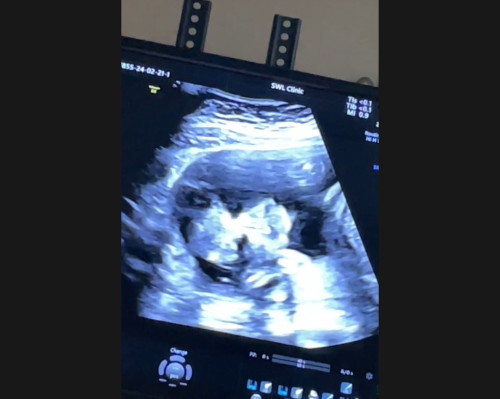

ภาพอันตร้าซาว

อันนี้คือหน้าน้องใช่มั้ยคะพอดีไปซาวเพศถ่ายคลิปมาลืมถามลุงหมอ

ก็เป็นไปได้ค่ะ เราท้องมาสามท้องแล้วดูภาพซาวด์ 2 มิติไม่ออกเลยค่ะว่าเป็นส่วนไหน 🤣

แก้มนุ้ยมากเลยค่ะแม่งื้แออออ

เค้าดูไม่เป็นไม่มั่นใจ แต่คิดว่าคือหน้าน้อง 😂